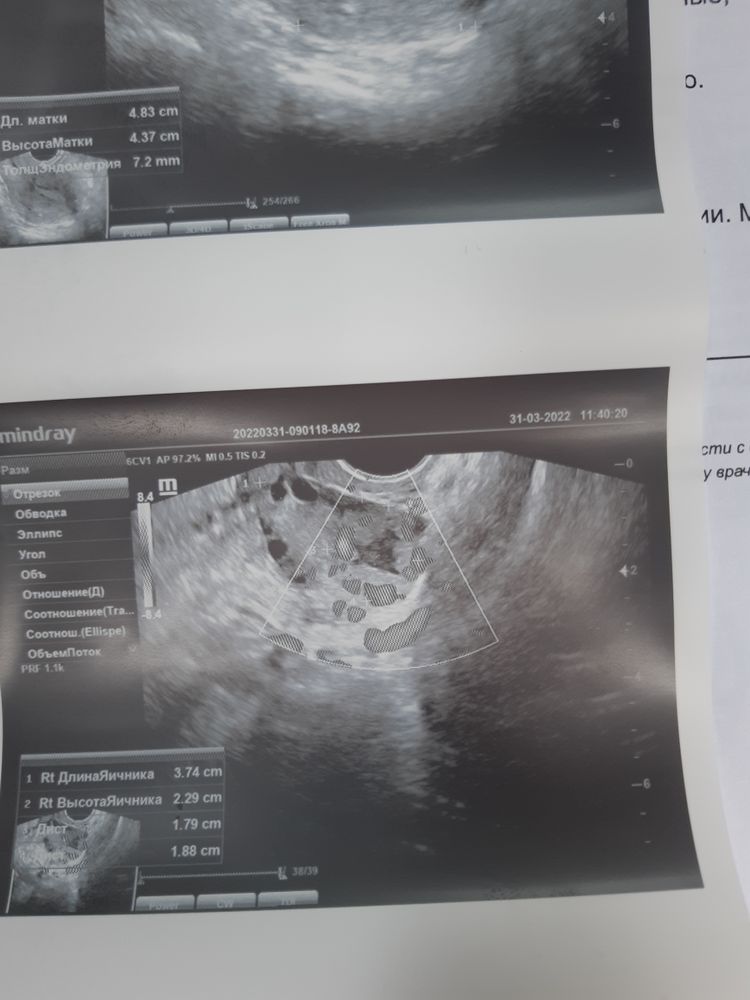

Изображение Изображение

Изображение Фото прикрепила .

Дюф не блокирует О кстати… вот вам весомое доказательство

Читаем все. Овуляция на 37 дц на последней таблетке Дюфастон